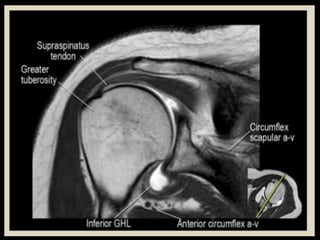

Hip Joint.

Shoulder

Joint.